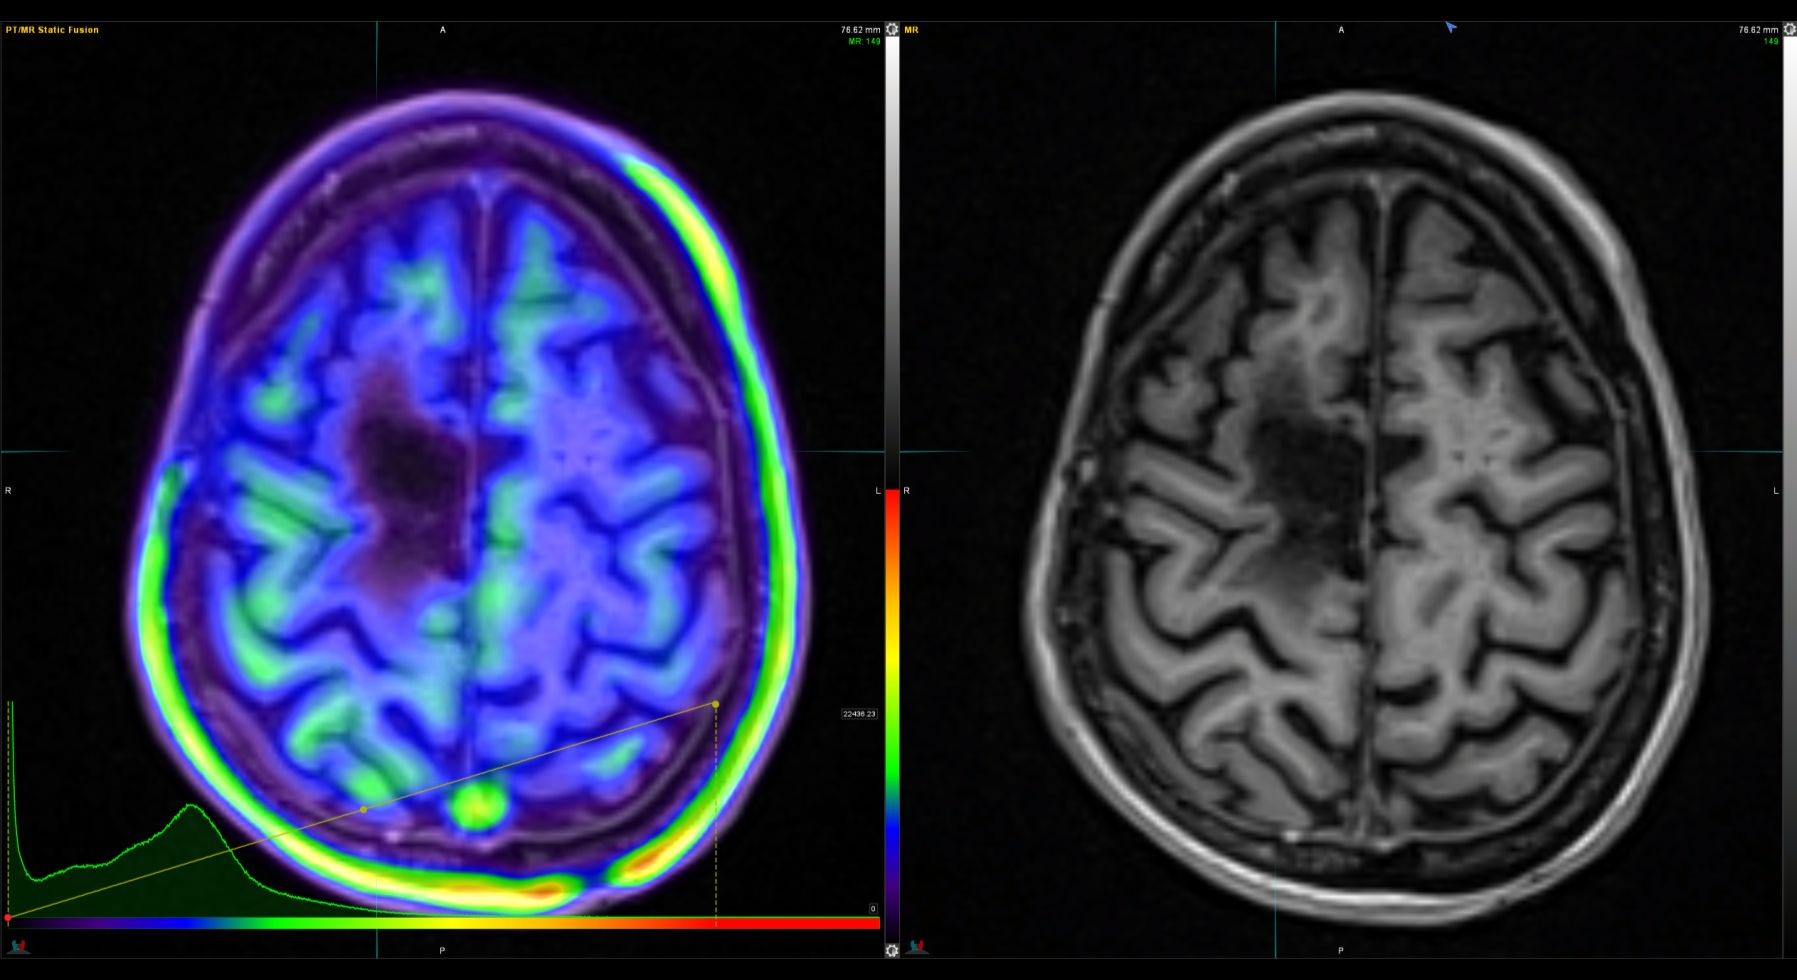

Η Τομογραφία Εκπομπής Ποζιτρονίων (PET) αποτελεί μια εξειδικευμένη μέθοδο της Πυρηνικής Ιατρικής που χρησιμοποιεί μοριακή απεικόνιση για να εντοπίσει και να παρακολουθήσει φυσιολογικές και παθολογικές λειτουργίες του οργανισμού. Συνδυάζοντας τη λειτουργική απεικόνιση της PET με την ανατομική πληροφορία της αξονικής τομογραφίας (CT), η υβριδική εξέταση PET/CT παρέχει εικόνες υψηλής ευκρίνειας και τη δυνατότητα ποσοτικής αξιολόγησης των βιολογικών μηχανισμών σε κυτταρικό επίπεδο.

Η PET/CT αποτελεί εξαιρετικά προηγμένη τεχνική της σύγχρονης ιατρικής απεικόνισης και χρησιμοποιείται τόσο για τη διάγνωση όσο και για την παρακολούθηση της ανταπόκρισης στη θεραπεία.

Οι κυριότερες εφαρμογές της αφορούν την ογκολογία, τη νευρολογία και, σε μικρότερο βαθμό, την καρδιολογία, ενώ συνεχώς αναπτύσσονται νέες χρήσεις σε άλλες ιατρικές ειδικότητες.

Με τη χρήση ειδικού λογισμικού Τεχνητής Νοημοσύνης (MIM – Lesion ID) πραγματοποιείται αυτόματος υπολογισμός της έκτασης και του όγκου των θέσεων ενεργού νόσου. Ξεπερνώντας τις δυνατότητες του ανθρώπινου οφθαλμού υπολογίζεται το συνολικό φορτίο νόσου πριν και μετά την θεραπεία επιτρέποντας ακριβέστερο χειρισμό του ασθενούς από τον θεράποντα ιατρό.